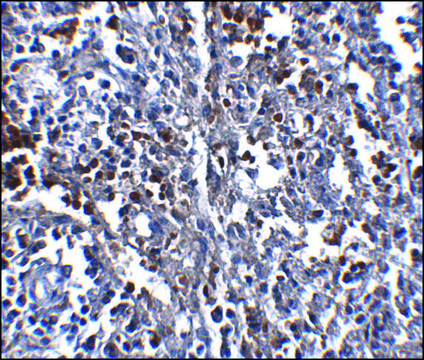

immunofluorescence: suitable, immunohistochemistry: suitable, indirect ELISA: suitable, western blot: suitable

General description

raised against a 16 amino acid peptide from near the carboxy terminus of human ORAI1.